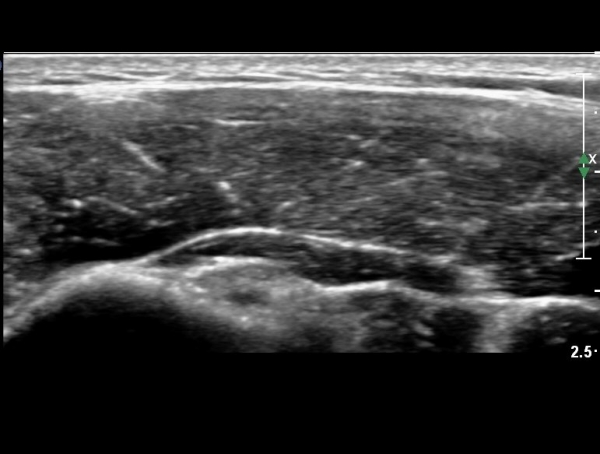

°ß°©ÇÏ±Ù°Ç Á¾´Ü¸ç°Ë»ç¿¡¼­ °Ç »óºÎ¿¡ ÀÌÁúÀûÀÎ ¿¡ÄÚ¸¦ º¸¿© °ß°©ÇÏ±Ù°Ç »óºÎ ºÎºÐÆÄ¿­ÀÌ ÃßÁ¤µÈ´Ù(»çÁø 3),

°ß°©ÇÏ±Ù°Ç ÇϺο¡¼­´Â ÀÌ»ó ¼Ò°ßÀÌ °üÂûµÇÁö ¾Ê´Â´Ù(»çÁø 4).